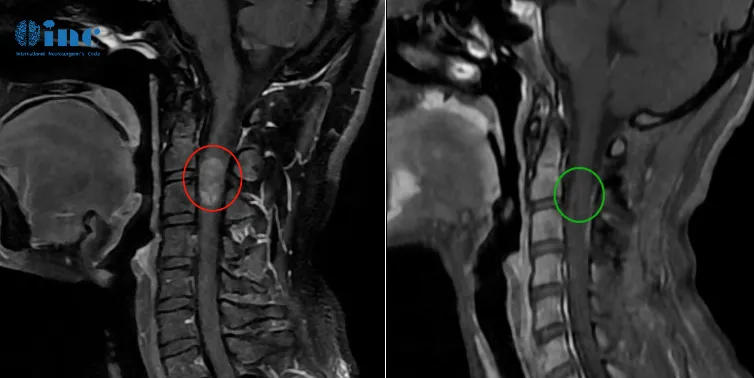

28岁女性-脊髓髓内室管膜瘤

28岁的潇潇6年前开始出现肩部至腰部疼痛,两年前,潇潇肩部后侧疼痛加剧,于当地医院行磁共振检查,提示髓内占位性病变,保守治疗无效。2021年7月行增强磁共振提示C3水平占位,直径7mm。当地医院排除炎性病变。因考虑到手术风险大,未作手术治疗。2022年10月磁共振提示8*12*19mm。年轻的潇潇害怕术后并发症,那咨询巴教授他是如何回答。

巴教授回复:

“在手术后会出现较坏的并发症是四肢麻痹。然而,在我以前的手术病例中,这从未发生过,所以,我并不认为在目前的情况下会有这么高的风险。有可能会出现运动功能恶化,但风险低于10%。也有可能出现手指和腿的感觉功能减退。膀胱功能在手术后一到两周内会受到影响。然而,上述的出现的新症状将逐渐消失并恢复正常。”

2022年教授疑难示范手术期间,INC巴教授成功手术,脊髓髓内肿瘤得到全切,无新发后遗症。

33岁女士-脊髓髓内室管膜瘤

"主要风险和较坏的结果是四肢瘫痪!幸运的是,我以前的类似肿瘤案例中从未出现过这种并发症。但我们都需意识到,这是一个需牢记的主要风险。因为我从未出现过,我估计这种风险小于1%。然而,运动和感觉障碍-就现在已经存在的-在术后会短时内加重,所以术后行走可能会出现困难,但是这在强化的物理治疗下会逐渐好转。此外,膀胱功能在术后早期阶段会出现障碍,但这也会逐渐好转。这些不是手术并发症,而是手术的副作用。"

术后12天查房,郑女士已经可以正常下地站立,肢体活动正常,除了右手稍微无力,术后3个月,在郑女士传来的康复视频里,她已经可以正常行走,术后无力的右手已经也可以正常抓握小物体、手部运动正常。